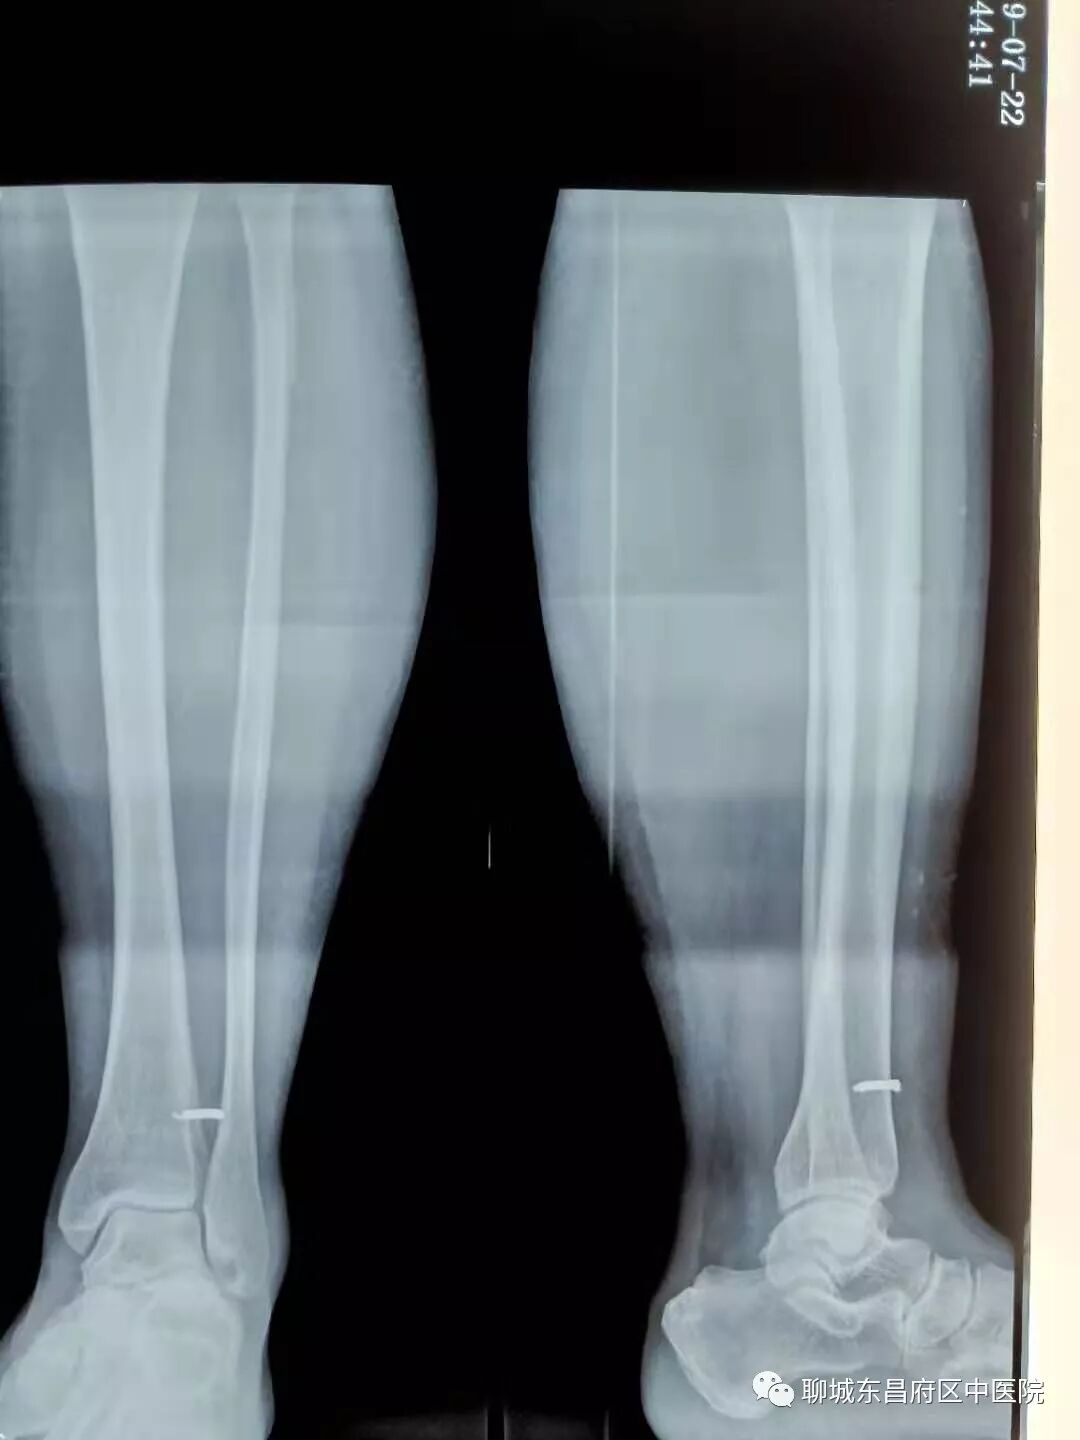

11岁的儿童马某,在玩耍时被建筑楼板上的细钢筋扎入右侧踝部,由120直接接入我院骨伤科,X线片示一枚约2.5毫米粗的钢筋在皮肤和骨骼内,贯穿腓骨和胫骨。患儿非常痛苦,家长也非常担心。乔洪杰主任立即召开科室人员进行讨论,决定在C型臂引导下将钢筋去除。手术中运用C型臂精确定位,完整将异物取出。 东昌府区中医院骨伤科乔洪杰主任温馨提示:夏天穿着衣物较少,容易受伤,做工和从事农活时务必小心谨慎。如有异物崩入体内,请务必及时到正规医院就诊,取异物时精确定位是关键,可以减少手术创伤,术后还需正规应用抗生素和肌注破伤风。